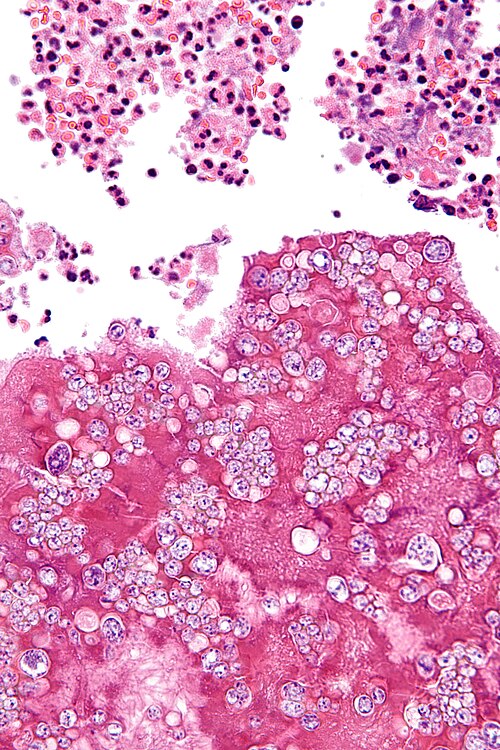

Low magnification. H&E stain.